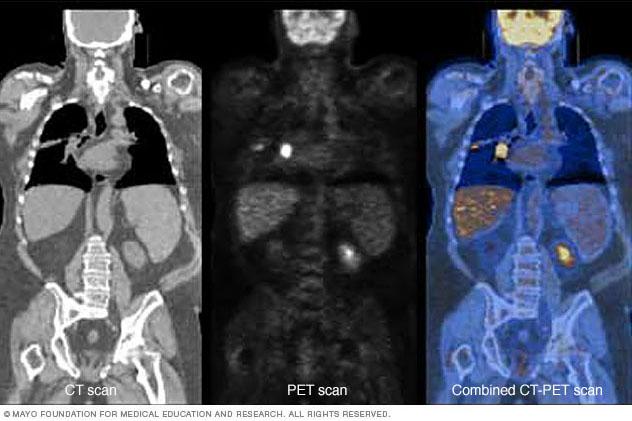

PET scan combined with CT scan

PET plus CT

Combining a PET scan with a CT scan can make the images easier for a healthcare professional to read. The image on the left shows a CT scan. The center image shows a PET scan. The image on the right shows a combined PET-CT scan. The bright area in the chest, seen most clearly on the PET and PET-CT images, shows lung cancer.